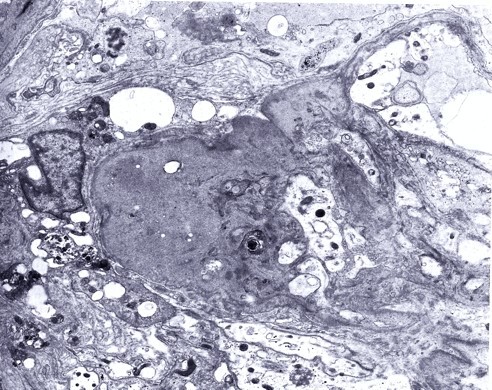

Electron microscopy:

Epithelial Cell Injury

- Foot process fusion

- Detachment from underlying basement membrane

Mesangial Changes

- Fibrosis

- Mesangial Matrix Increase

- Insudative deposition of IgM and C3

- Lipid vacuoles